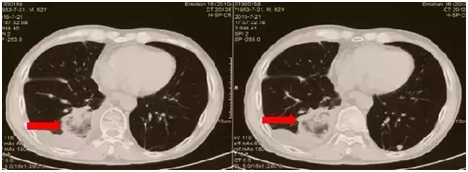

就在这时,有位医生建议他可以试一试PD-1抑制剂免疫治疗,通过美国的朋友,他购买到PD-1抑制剂,在接受第一次注射的三周后,李先生的饮食、精神状态有了很大的改善。他又可以神采奕奕的出门了,和三周前的他简直判若两人。甲胎蛋白也大幅度下降至三万多。第二次注射以后,甲胎蛋白降至两万。更为神奇的是,肺部转移病灶减少了50%-60%(见图1,图2)。现在,李先生按时接受每三周一次的PD-1抑制剂的治疗,除了,第二周期后出现转氨酶的一过性升高以外, 没有出现其他不可耐受的副作用。

图 1 PD-1治疗前,红色标示肿瘤

图2 PD-1治疗后